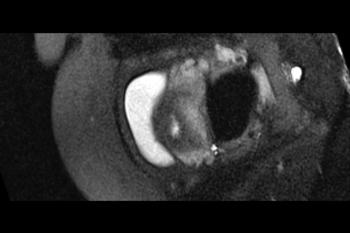

Figure 6. Images obtained in the case of a 24-year-old woman pregnant with twins, with characteristic rash at 9 weeks of pregnancy and confirmed Zika virus infection. (For each pair of images, the first image is of twin A, and the second image is of twin B.) At 14 weeks of gestational age, the fetal head size of both twins was normal. The head size never went below the 3rd percentile for either fetus in examinations at 19–28 weeks. (a, b) Sagittal and (c, d) axial fetal MR images were obtained at 36 weeks. (e, f) Axial and (g, h) surface reconstruction postnatal CT images and (i, j) axial T2-weighted and (k, l) coronal MR images were obtained 1 week after delivery at 38 weeks of gestational age. There is severe microcephaly with profound frontal lobe hypoplasia. Calcifications in the subcortical white matter at the gray matter–white matter junction are visualized. Both twins have a flattened appearance of the pons. The spinal cord is atrophic (best seen on a). Redundant skin is seen in the occipital region. There is polymicrogyria involving the frontal and parietal regions and atrophic cortex and white matter in the occipital regions. Each twin has hypoplasia of the corpus callosum, with prominent fornices. There is abnormal myelination in the occipital region that, in twin A (i), has the appearance of a cyst or septation within the ventricle. The cerebellum is somewhat small and nodular. There is lack of rotation of the hippocampi.